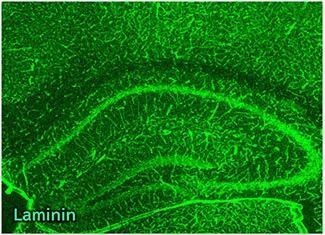

性能数据

物种:小鼠

部位:海马体

样品:冰冻切片

抗体浓度:1:500

数据提供:京都工艺纤维大学 应用生物学系 宮田老师